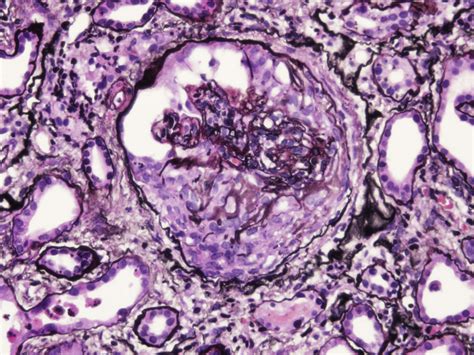

Infective Endocarditis Gn

Infective Endocarditis Gn, or Infective Endocarditis of the native heart valves, is a specific form of the condition that affects the heart's natural valves. This type of Infective Endocarditis is more common than Infective Endocarditis affecting prosthetic valves and can occur in individuals with no prior history of heart disease. The diagnosis and treatment of Infective Endocarditis Gn follow similar principles to those of Infective Endocarditis in general, with a focus on early detection and appropriate antibiotic therapy.